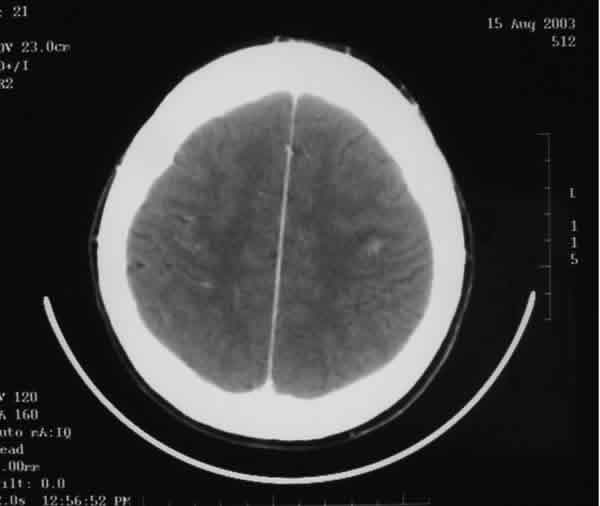

Fig. 5. En este corte de la TC craneal se pueden

apreciar múltiples focos metastásicos cerebrales.